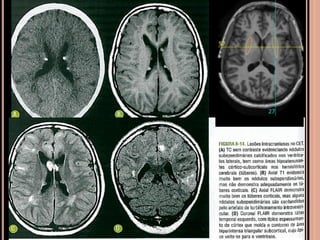

Achados de imagem

CET

Achados de imagem – Ressonância magnética

 Recomendações

RM: método de escolha;

anual em paciente com CET e nódulos

subependimários adjacentes ao forame de Monro,

parcialmente calcificados e com impregnação pelo

Gd (crescimento e obstrução)  favorece ASCG e

indica cirurgia precoce;

TC sem contraste: só para ver nódulos

subependimários calcificados;